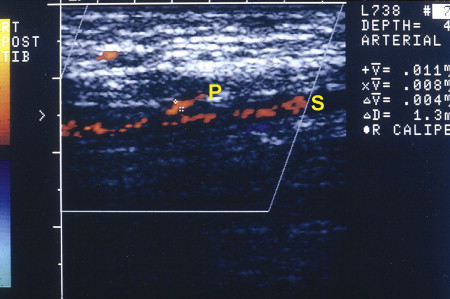

Depending on the orientation of the color duplex imaging transducer, the vessel orifice can be calibrated and peak systolic flow velocity determined from concomitant pulse-volume recordings; the take-off of perforators from the source vessel identified ( Fig. 3 ); and the perforator intramuscular, subfascial, or epifascial course documented.